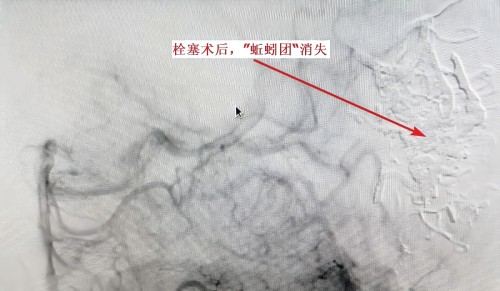

后贺嗲经朋友介绍来到捷克论坛 介入血管外科就诊,以脑动静脉畸形伴左枕叶出血收入院。因患者高龄,基础疾病多,且动静脉畸形范围较大,一次性手术风险很大,刘放其、康超文副主任医师团队决定分两次手术治疗。第一次手术,行颅内动静脉畸形部分栓塞术,术后第二天自行下床活动,视力模糊症状消失,恢复正常生活。11月11日,贺嗲进行第二次手术治疗,将残余畸形血管进行栓塞。刘放其副主任医生团队凭借精湛技术和丰富经验,成功完成手术,患者于11月16日出院。

最后刘放其副主任医师提醒大家:打麻将容易导致疲劳、情绪激动、血压波动大,每年在牌桌上发生的脑卒中的病例都屡见不鲜,尤其患有脑血管病的病人,更容易发病。脑血管畸形是一种先天性脑血管发育异常,主要表现为颅内动脉及静脉之间的异常连接,形成异常的血管团。这些异常血管团可能会对周围脑组织造成压迫,引起神经功能障碍,也可能会破裂出血,导致脑出血。此外,脑血管畸形还可能导致其他神经系统症状,如头痛、头晕、肢体麻木、无力等。如果出现视力模糊等症状,建议及时就医,进行头部CT、磁共振成像等,确定病因,采取相应治疗措施。(介入血管外科二病区 邓智超)